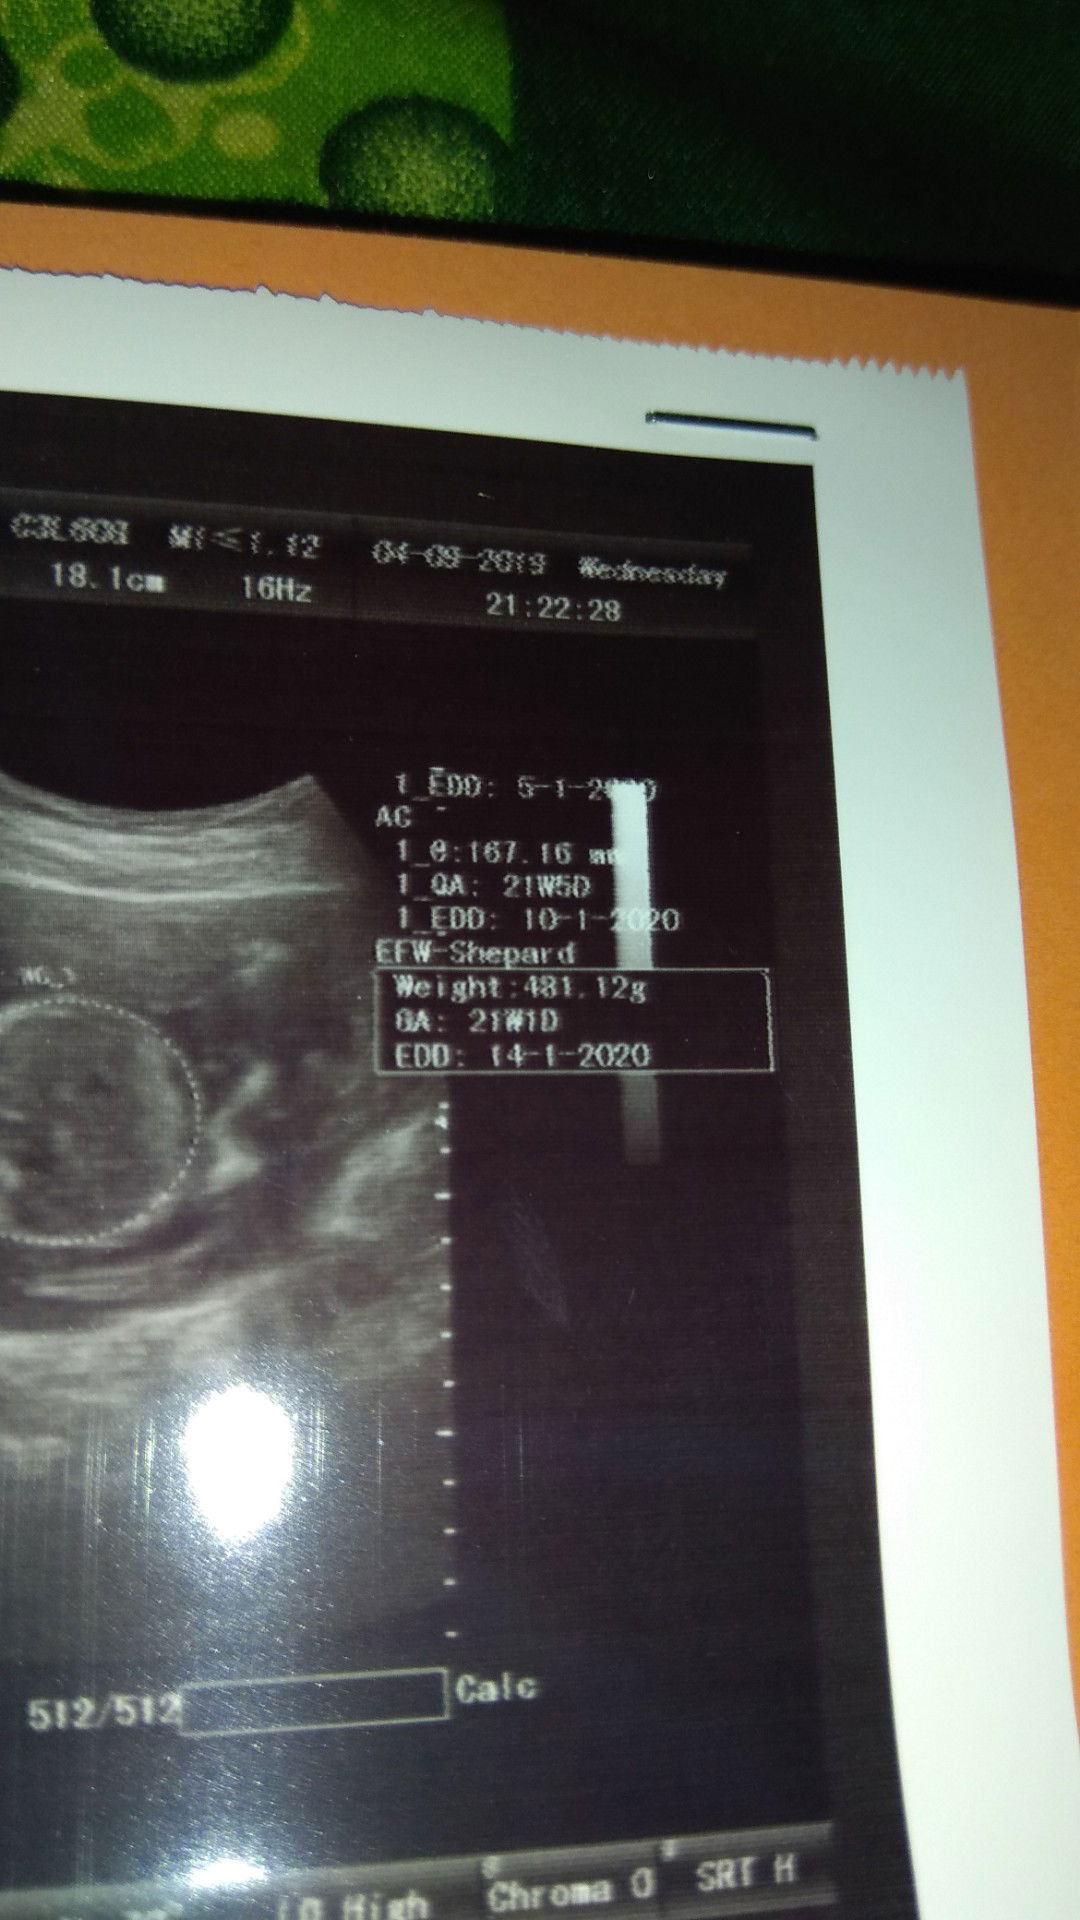

Bener bener tadi gag puas ama dokternya soalnya d tanya hanya bilang bagus... Ada yg maksut gag ya kenapa usia kandungannya beda atas ama bawah.. Yang bner mana ya.. Terus peekiraan lahir jg beda Ada yg maksut gag ya knp bgtu

Beda2 itu krn usg kan ngitungnya berdasarkan panjang tangan, kaki, pelipis, ukuran perut baby bun. Klo mau tau hpl, ikutin berdasarkan hpht aja atau usg paling awal.

Atas bawah gpp beda asal jgn lbh dari 2 minggu. Ac itu usia khmilan bdsrkn ukuran badan. Klo bpd berdsrkan uk kepala bayi

Itu beda berdasarkan perkiraan hpl dr dokter sama usia berdasarkan USG,ga akurat sama,beda beberapa hari biasanya

Perkiraan lahir memang beda² itu dilihat dari lingkar kepala panjang badan dll. Yang mendekati akurat USG tm1 ya